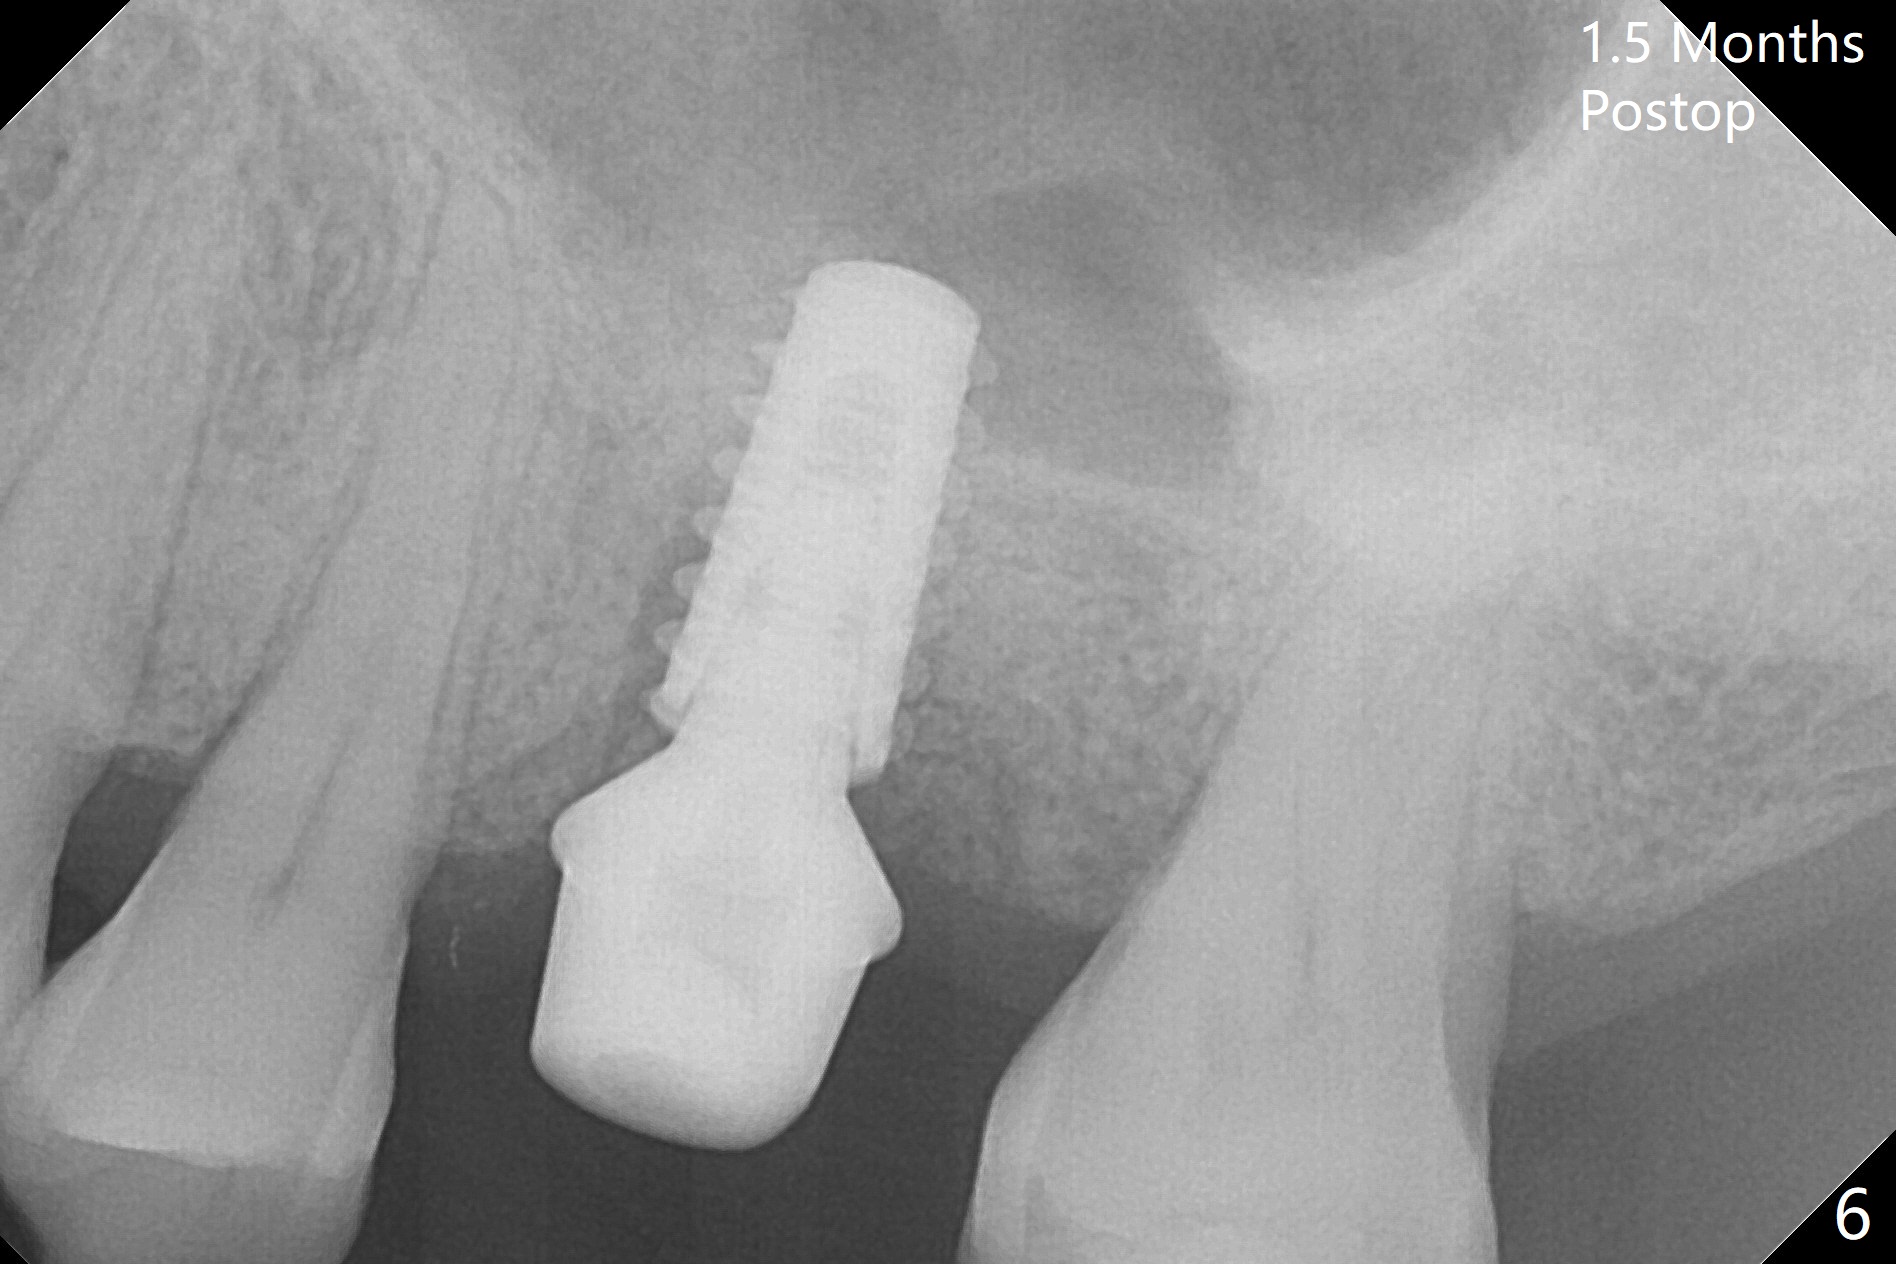

After extraction of the tooth #14 with palatal root fracture (Fig.1 <), sinus membrane perforation is found in the buccal wall of the palatal socket (Fig.2 ^). Osteotomy is initiated in the buccal strut of the septum (Fig.3 *). As the osteotomy increases in diameter, it slides into the mesiobuccal socket (Fig.4). A 5x9 mm implant is placed slightly mesial; after placement of a 6.5x4(2) mm abutment and insertion of collagen plug in the palatal socket, Vera graft is placed in the remaining socket space (Fig.5 *). Nasal hemorrhage persists 1.5 months postop (Fig.6). The distal gingiva is slightly tender and erythematous; a 6x4 mm healing abutment is placed 2.5 months postop (Fig.7,8). Impression is taken after laser gingivectomy 3.5 months postop. The patient feels discomfort at the site 7 days post impression, although the gingiva heals after laser treatment. Two weeks after cementation, the mesial gingiva is mildly tender and the abutment screw is loose. A 6x3 mm healing abutment is placed. The abutment/crown is reseated 10 months postop (Fig.9).